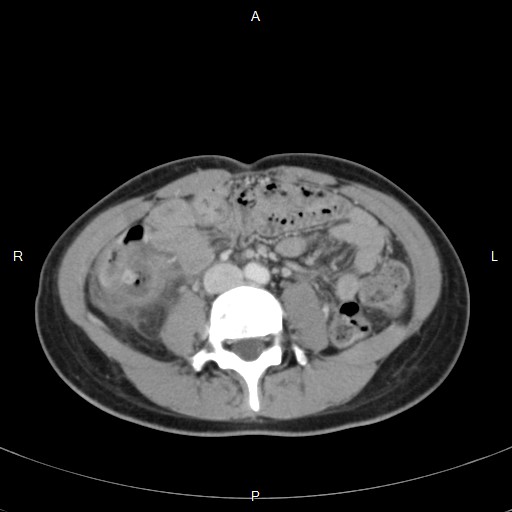

在沒有注射顯影劑的升結腸可見一高亮度的糞石和週邊的發炎變化,

在注射顯影劑的CT下,可以看到卡在憩室的糞石週邊有一些液體和氣體存在。

在隔日的超音波可以看到和第一天不同的地方,

憩室內的糞石仍在,

憩室內低回音的液體增多,

憩室內高回音的空氣出現了,

週邊高回音腸繫膜脂肪範圍對擴大的更加明顯了。

此時由Cefmetazole改為Avelox來治療這個腹腔內的發炎。